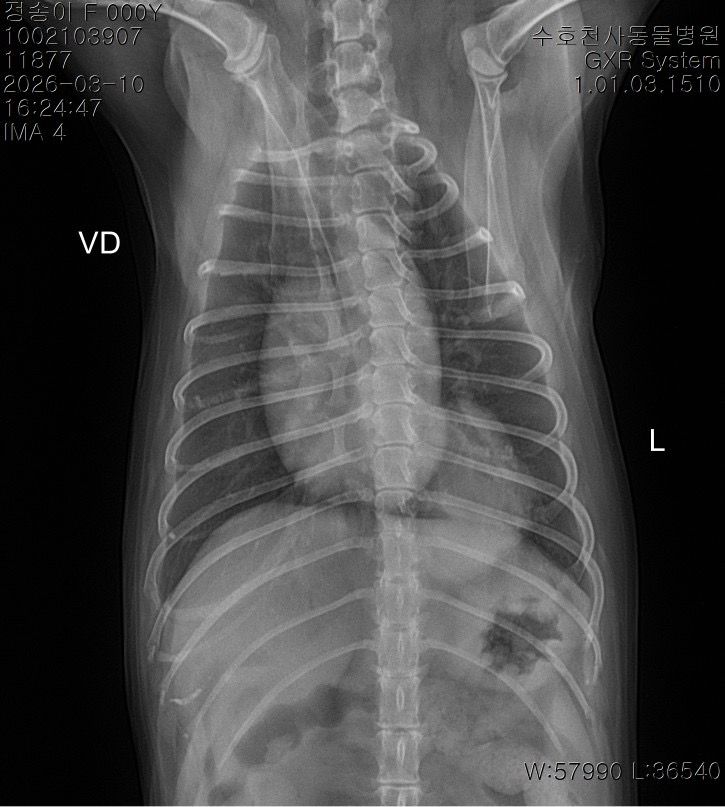

말씀주신 것처럼 보여주신 방사선에서 흉강 내 종양 (폐, 흉강 등)이 의심되는 상황입니다. 다만 방사선 사진만으로는 종양 여부와 정확한 위치, 개수, 성격을 완전히 판단하기 어렵고 CT 촬영을 통해 정확한 판단이 이루어져야 수술 여부 등을 결정할 수 있습니다. 좌측 폐는 앞엽과 뒷엽으로 나눠지긴 하고, 사진 상으로는 좌측 뒷엽 혹은 오른쪽 폐와 왼쪽 폐 사이에 있는 덧엽 부분에도 종괴가 위치하는 것으로 보이지만, 방사선으로는 어느 폐엽에서 발생한 것인지 정확히 구분할 수는 없습니다.

종괴가 단일 병변인지 여러 개인지, 정확히 어느 폐엽에서 시작되었는지, 주변 조직이나 다른 폐엽으로 이어져 있는지,

원발성 종양인지 전이성 병변인지 등을 알려면 CT 촬영이 필요하며 치료 방향도 CT 결과에 따라 달라집니다. 만약 한 두개의 폐엽에 국한된 단일 종괴라면 경우에 따라 해당 폐엽을 제거하는 수술을 고려하는 경우가 있습니다. 하지만 주변 조직으로의 침습, 원격전이 혹은 너무 많은 엽을 포함하고 있어 수술 후 호흡 합병증이 예상되는 경우 수술로 완치 기대는 어렵습니다. 빠른 CT 촬영을 추천드립니다.

사진상으로는 상당히 전형적인 원발성 폐종양의 방사선 양상이지만 말씀 하신 "방사선 엑스레이 촬영 한 것을 통해서서도

폐 종양인지 아닌지, 갯수를 확인가능한지

한 폐엽에만 있는 상황인건지 아니면 윗쪽 중간 폐엽과도 이어져있는지 원발성,악성 등등"에 해당하는 내용은 방사선 사진으로 평가하는게 아닌 흉부 CT검사로 확인해야 하는 사항들입니다. 흉부 방사선 검사는 저렴하지만 정확도와 세밀한 내용 평가에 제한이 있습니다. 우선 주치의와 상의하시고 흉부 CT검사를 촬영 한 후에 침습이나 전이 여부 평가하고 수술 계획 잡으시기 바랍니다. 원발성 폐종양인 경우 악성이더라도 수술로도 완치가 가능한 몇 안되는 질환이니 수술을 빨리 하면 할 수록 좋을 수 있으니 아이에게 주워진 시간을 아끼시기 바랍니다.